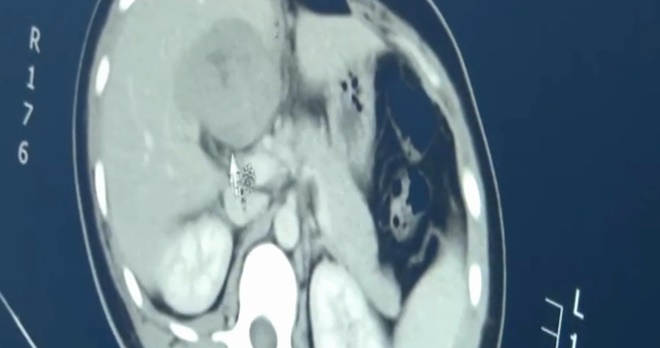

但在超音波的检查下,子宫竟找不到任何胚囊,让医生高度怀疑是「子宫外孕」,经电脑断层扫描(CT)检查下,竟发现肝脏竟然「受精」了,上面形成一个肿块胚胎,医生整个吓到了。

医生不论怎么检查尤女子宫,都没有发现任何胚囊,怀疑是子宫外孕,赶紧做电脑断层扫描(CT)检查,竟发现肝脏部位有胚囊,长出一大块肿块,病例超级罕见。

医生李士华透露,病患已停经3个月,经血液后证实怀孕,但子宫里面却找不到胚囊,最后在肝脏找到了,「肝门附近有一个大的肿块,盆腔里少量积液,当时就有怀疑病患是肝脏妊娠受精。」